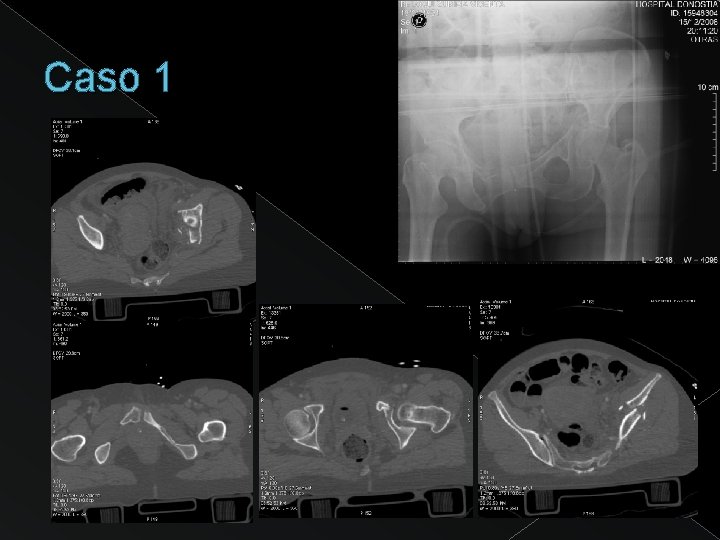

Caso 1

Disrupción del anillo obturador + extensión a pala iliaca FRACTURA BICOLUMNARIA